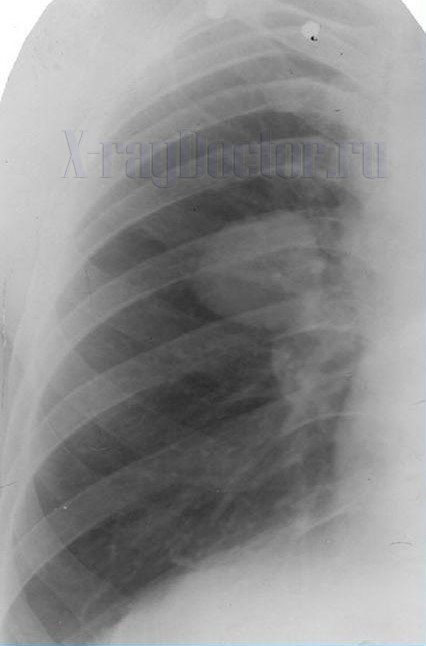

Ретенционная киста легкого на рентгеновском снимке выявляется по следующим признакам:

- Тонкостенная округлая тень.

- Неровный наружный контур за счет соединительной ткани.

- При наличии воздуха внутри полости прослеживается уровень жидкости.

Ретенционные кисты образуются при закупорке бронха мокротой, опухолью и инородным телом. При этом вздувается проксимальная часть бронхиального дерева. На рентгенограмме образование представлено кольцевидной тенью неправильной овальной формы, которое с одной стороны имеет дугообразное закругление (место закупорки).

Ретенционная форма образования имеет вид «ветки дерева» — один центр с многочисленными разветвлениями. Из-за специфичности строения контуры полости полициклические, волнистые или бугристые и тонкие. Вокруг тени деформируется легочной рисунок. На снимках, выполненных в разные фазы дыхательного цикла, форма и контуры образования не изменяются.